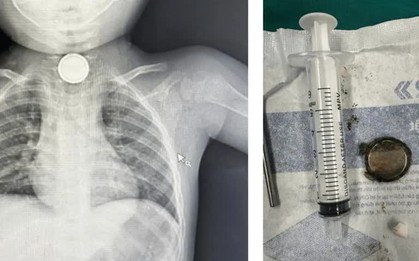

Bé trai bị hoại tử niêm mạc thực quản do nuốt cục pin

Bệnh viện Nhi đồng Thành phố (TP Hồ Chí Minh) vừa tiếp nhận một trường hợp bé trai 21 tháng tuổi, nuốt phải dị vật nguy hiểm.